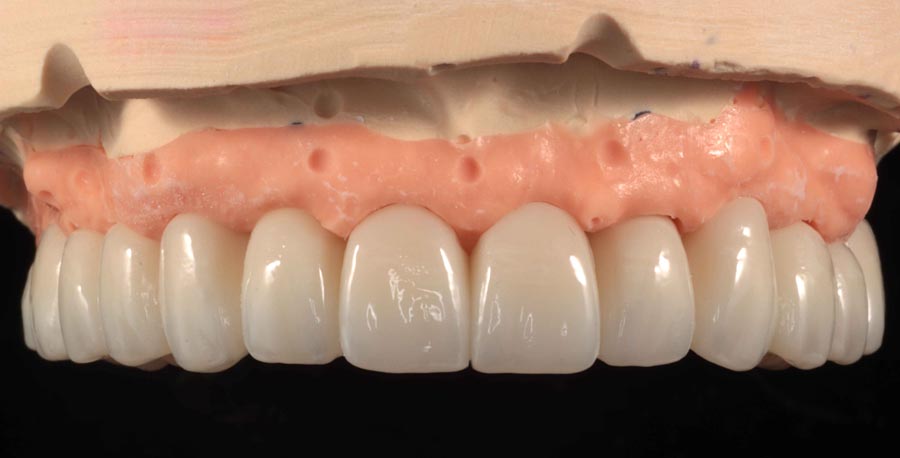

Prototype wax-up, frontal. Any imperfections or patient requests are changed in this prototype stage.

Right transition. We photograph the “transition” from prototype to gums in the event there have been changes since the final impression. Sweat every detail!